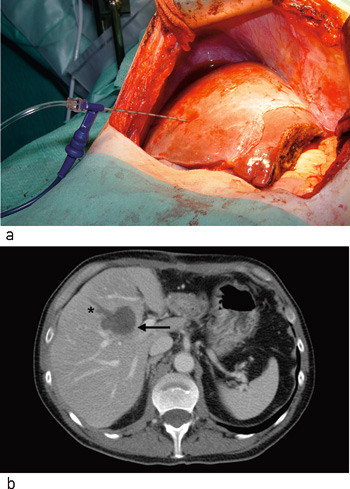

To ulike systemer for radiofrekvensablasjon ble brukt i perioden. Et system med perfusjonselektroder (Elektrotom HiTT 106, Berchtold GmbH & Co, Tuttlingen, Tyskland) ble benyttet til de første 11 pasientene. Fra 2005 benyttet vi et system med paraplyelektroder (RITA model 1500, RITA Medical Systems, Mountain View, CA) (fig 1). Kontrastforsterket ultralyd (n = 12), intraoperativ ultralyd uten kontrast (n = 4) eller MR (n = 1) ble brukt for å plassere elektroden og monitorere utbredelsen av vevsødeleggelsen. Optimal elektrodeposisjon ble bestemt ut fra elektrodens karakteristika samt tumors geometri og beliggenhet i forhold til intrahepatiske kar. Ablasjon ble gjennomført når elektrodeposisjonen var akseptabel.

Etter avsluttet ablasjon ble vevsskaden vurdert. Ablasjonen ble ansett for å være adekvat hvis både tumor og en randsone på minst 0,5 – 1 cm rundt tumor var behandlet. Elektroden ble reposisjonert hvis tumor ikke ble oppfattet som adekvat behandlet. Det ble gjort henholdsvis to (n = 13), tre (n = 3) eller fire (n = 1) elektrodeplasseringer. Stikkanalen ble koagulert ved hver reposisjonering for å unngå implantasjonsmetastaser. Figur 2a viser en perfusjonselektrode posisjonert i en tumor. Postoperativt ses et velavgrenset område som ikke lader opp kontrastmiddel (fig 2b).